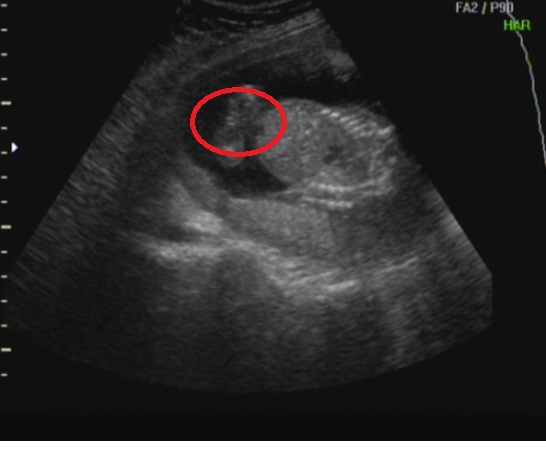

Örülök, hogy még mindig láááááány!!!! Nálunk annyira egyértelmű volt a 16. heti UH-n, hogy ha nem láttak semmit, akkor lassan kezdd elhinni!